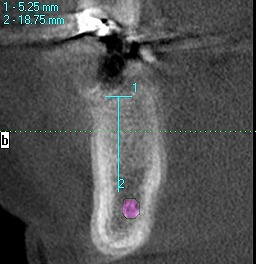

術前のCTになります

5mmの11,5mmというインプラントを埋入しています